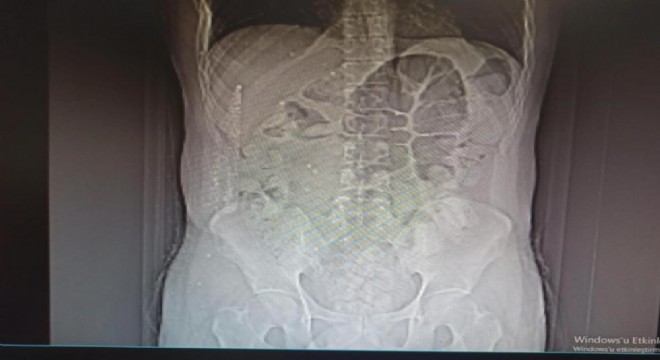

İl Emniyet Müdürlüğü Narkotik Suçlarla Mücadele Şube Müdürlüğü ile Kaçakçılık ve Organize Suçlarla Mücadele Şube Müdürlüğü ekiplerince yapılan ortak çalışmada; uygulama noktasında durdurulan, İran otobüsünde yolcu olarak bulunan İran uyruklu şüpheli M.K. (31) isimli kişiye yapılan tomografi çekiminde mide ve bağırsak kısmında uyuşturucu olabileceğini değerlendirilen çok sayıda yabancı cismin olduğu tespit edildi.

Yapılan tetkikler neticesinde M.K.’nın midesinden 64 parça halinde 711,86 gr gelen Afyon Sakızı ele geçirildi.